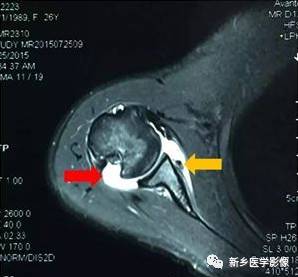

病例三:

红色箭头:肱骨头后方骨缺损(Hill-sachs损伤)

黄色箭头:关节盂前下方Bankart损伤